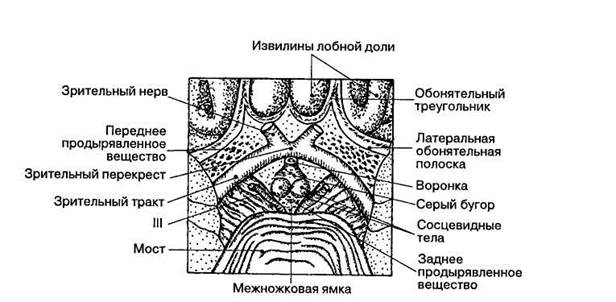

Необычные объекты: Переднее продырявленное вещество